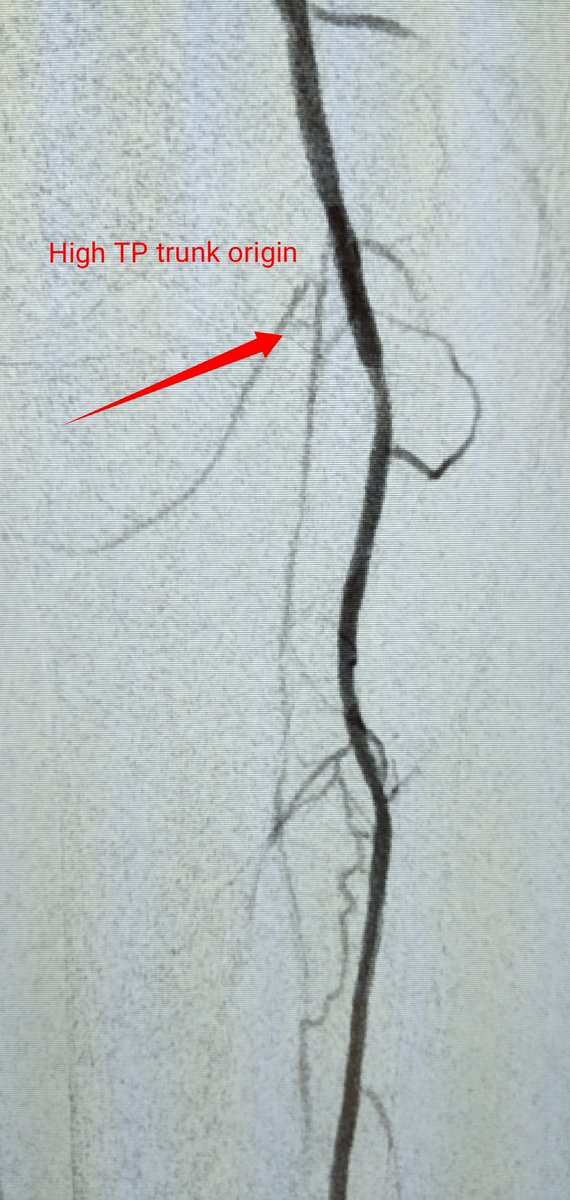

84 yo F RC4 #CLI @AbbottGlobal #commandwire to cross @MedtronicAPV #HawkoneS to debulk @BardPV #Lutonix DCB. #nometal @kmadass @SDhandMD @Mustapja @keithppereira @SriniTummala @AlexCVIR @FadiSaab17 @LessneVIR @Heartpower717 Opinions on @BardPV poor Lutonix data in women?